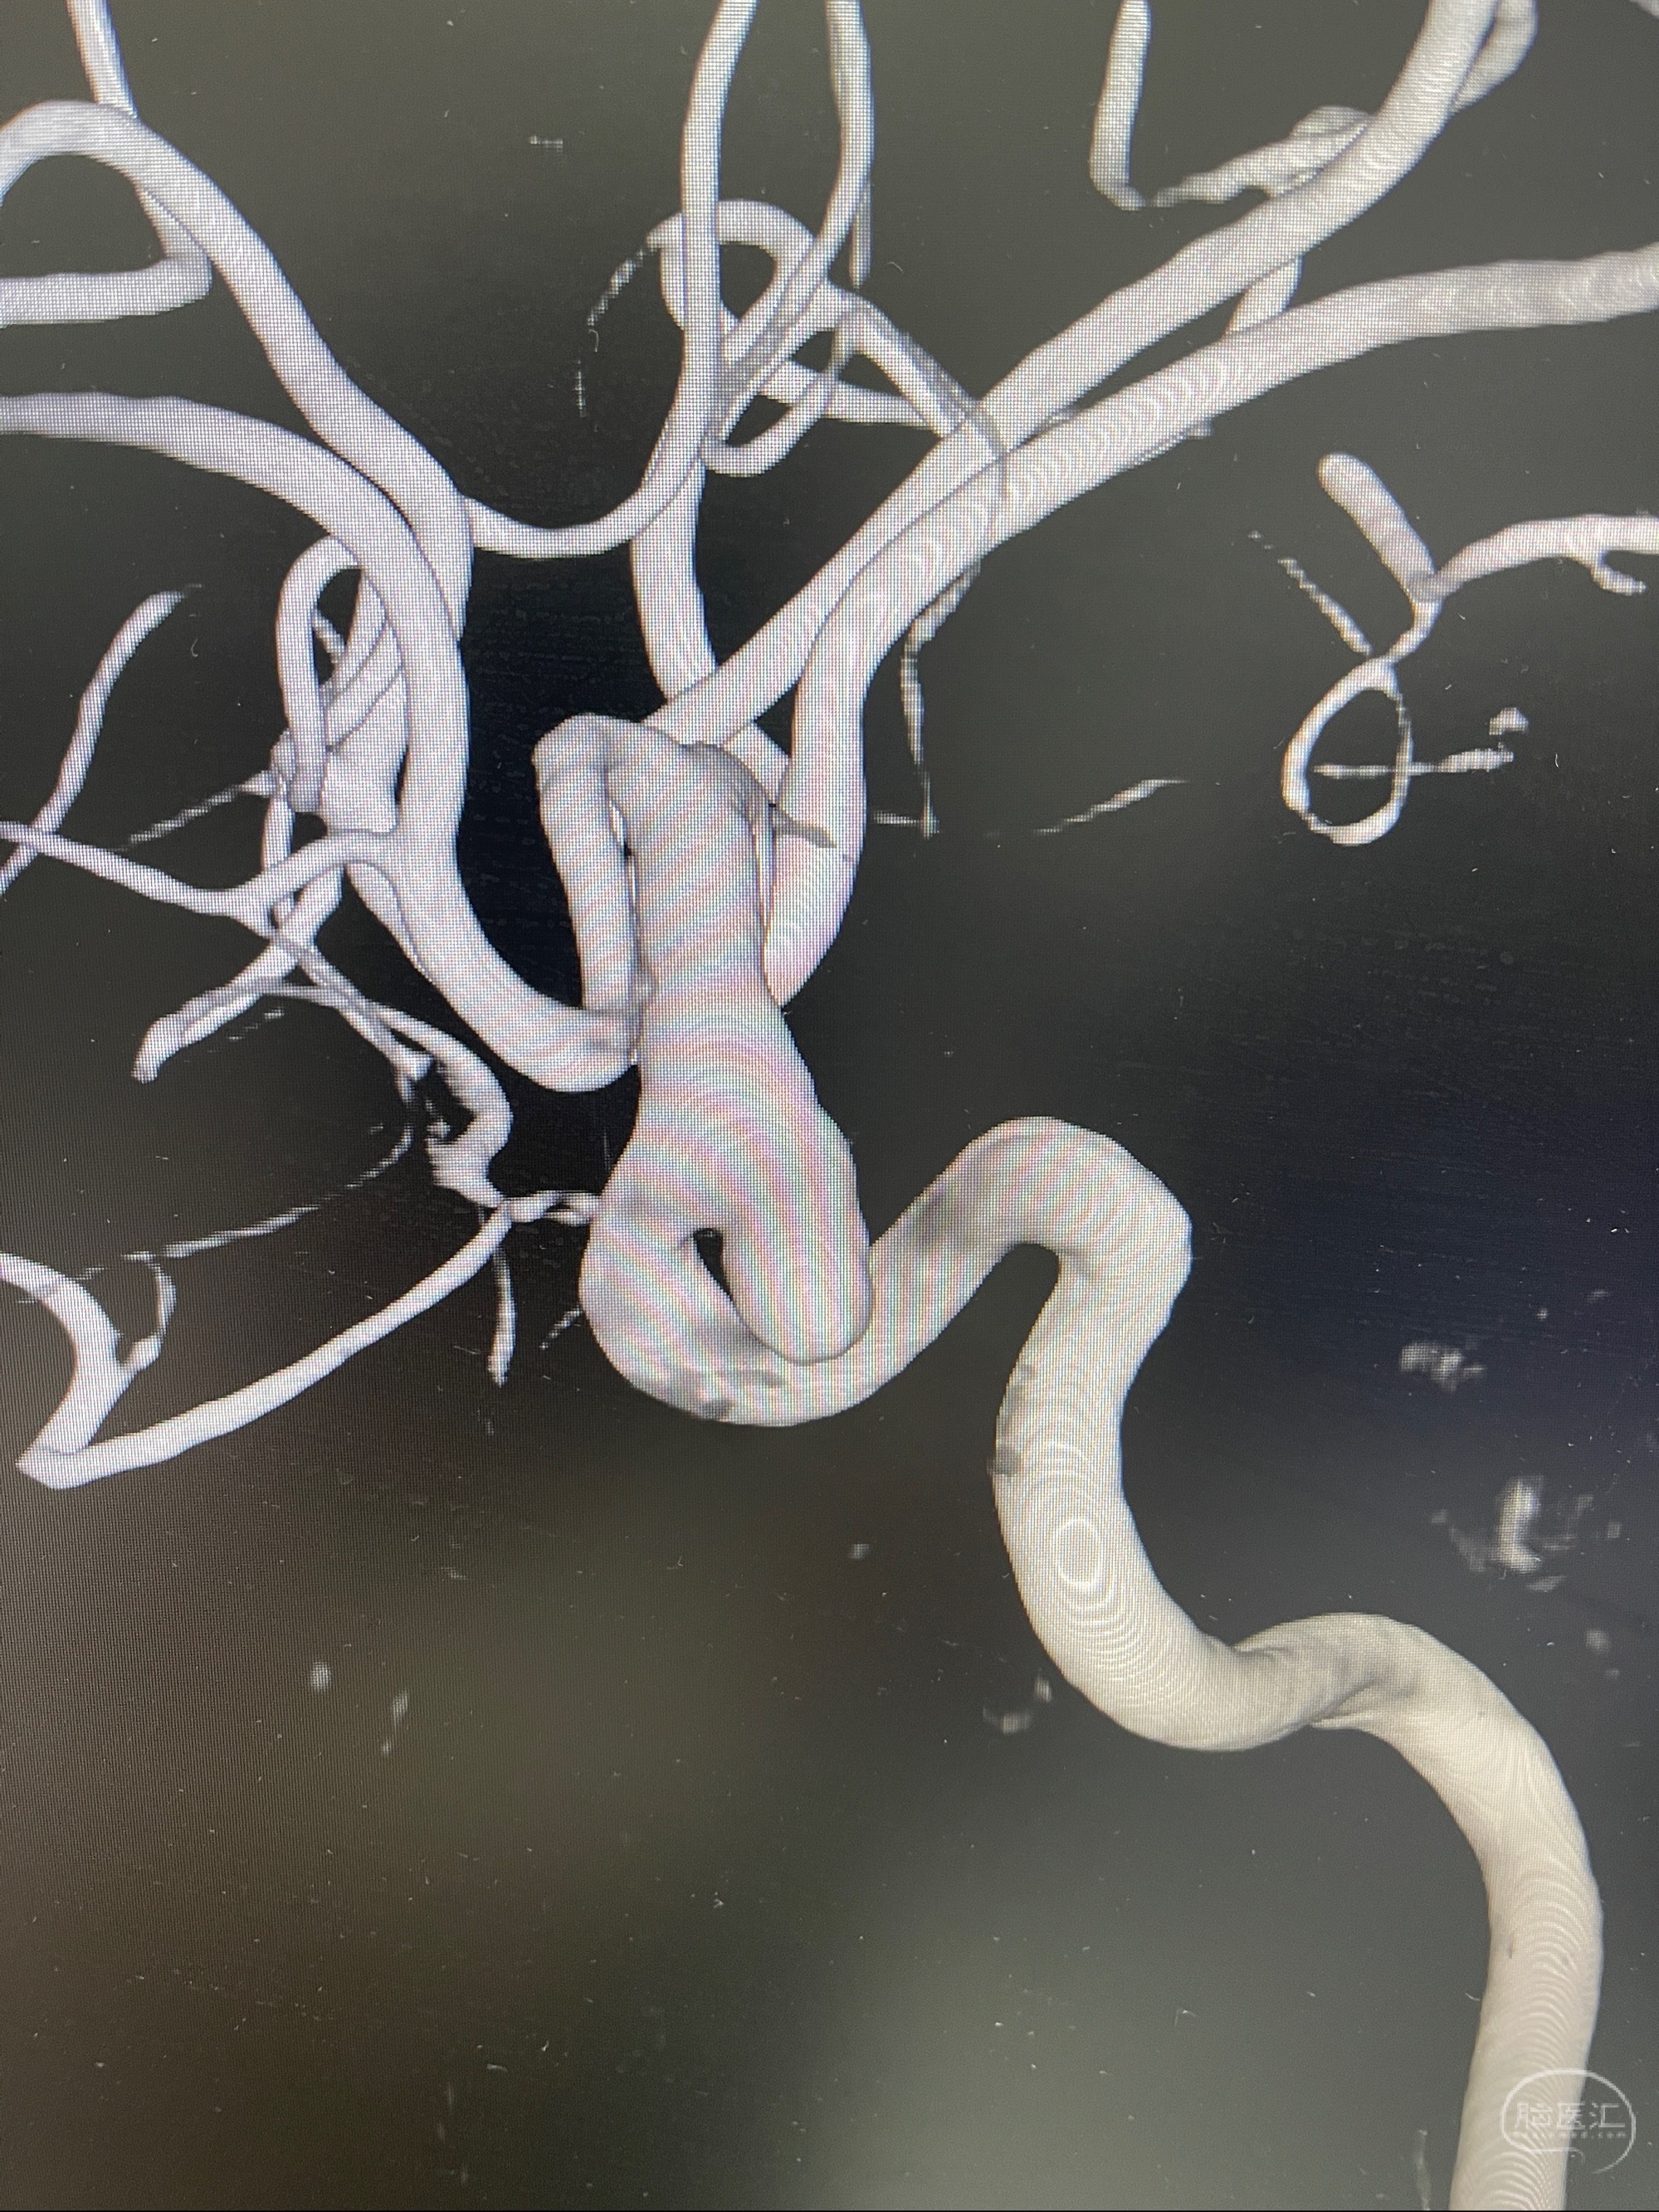

2023.07.25 泰州市人民医院查头颅CTA提示右侧C6段瘤样突起,建议DSA检查;

CTA示:右侧颈内动脉C6段见指向下方的突起,余左侧颈内动脉、双侧椎动脉、大脑前动脉、大脑中动脉、大脑后动脉及基底动脉走形正常,未见明显扩张及狭窄,局部未见明显瘤样扩张。

看原图,应该有两侧动脉瘤😅

2023-07-27全脑血管造影:双侧颈内动脉眼动脉段动脉瘤,右侧较大